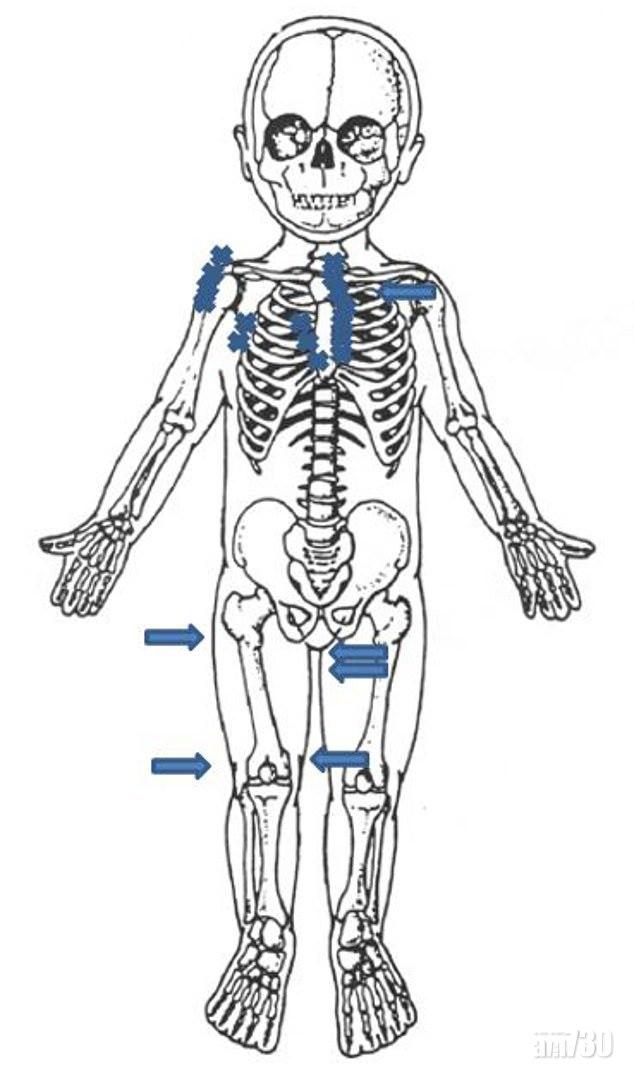

男嬰手臂骨折斷,令人看得心痛。(互聯網)

顯示男嬰骨折情況的電腦繪圖。(互聯網)

點可以對子女咁殘忍?!英國布賴頓(Brighton)一名4個月大男嬰慘被惡父母家暴,手臂、肋骨、膝蓋、腳踝等全身28處骨折,估計送院前4至6周持續受虐,兒科專家指,從傷勢判斷,男嬰一些骨被人像扭毛巾般扭斷。案發於17年,有家暴案底的男子建卓札克(Adam Jendrzeczak)與女友柯賓絲卡(Aleksandra Kopinska),將4個月大的男嬰送院,報稱他被地毯絆倒而跌斷手臂,但醫生發現男嬰身體多處骨折,明顯由強大外力造成,於是報警,警方以虐兒罪拘捕兩人,兩人其後被裁定16年11月至17年2月期間虐待兒童罪成,案件周一宣判。